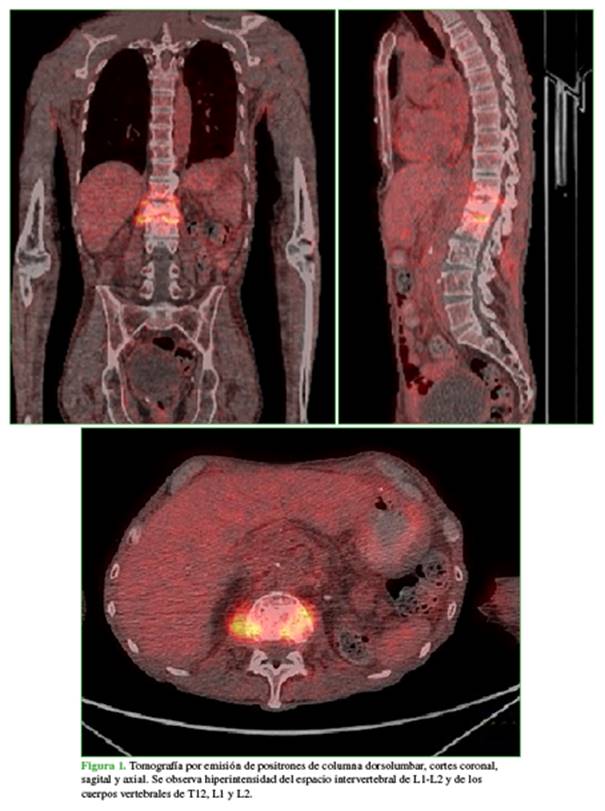

A su vez, se realizó una resonancia magnética sin contraste, debido a la enfermedad renal severa, que reveló hiperintensidad de L1-L2 y se descartó un cuadro compresivo (Figura 2).